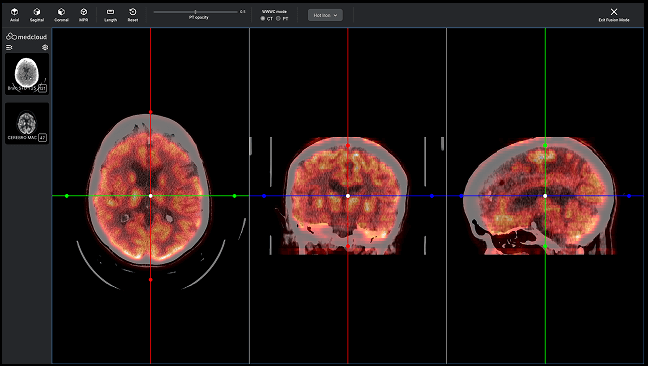

La fusión DICOM PET-CT permite la combinación y sincronización de ambas en una sola imagen o conjunto de datos. Realice análisis más completos superponiendo información metabólica de PET sobre estructuras anatómicas visualizadas por TC para una mejor localización y caracterización de anomalías, como tumores, proporcionando información funcional y estructural en una sola imagen.